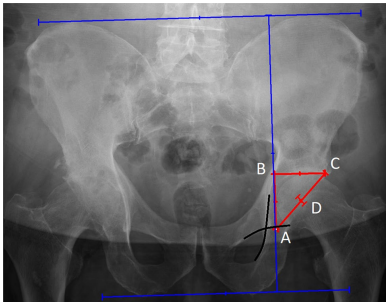

Ranawat法是一种古老但至今仍适用的确定COR的方法。要在骨盆前后位 (anteroposterior, AP) X线片上确定旋转中心,必须画两条水平线:一条在髂嵴 (iliac crests) 水平,另一条在坐骨结节 (ischial tuberosities) 水平。这两条线必须通过一条垂直线连接,该垂直线穿过一个点,该点位于Köhler线和Shenton线交点外侧5 mm处。点B和点C位于沿髋臼杯软骨下顶 (subchondral roof of the cup) 水平的水平线上。点B距离点A和点C相等。COR位于AC线长度的一半处。

COR的确定。 A. 位于Köhler线和Shenton线交点外侧5 mm的点; B. 位于髋臼杯软骨下顶水平的水平线上的点;距离点A和点C相等; C. 位于髋臼杯软骨下顶水平的水平线上的点; D. 位于AC线长度一半处的点。